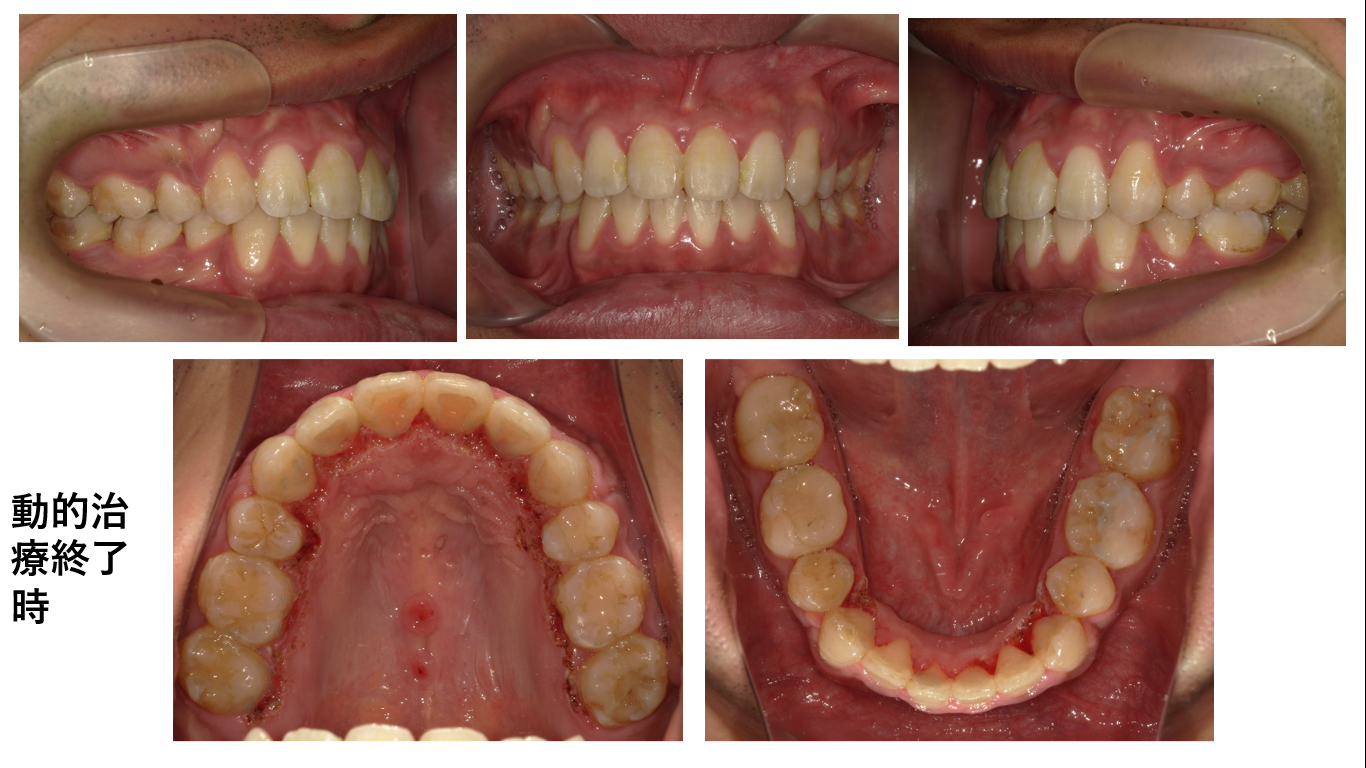

矯正症例 140 AngleⅠ級上下顎前突、舌側矯正,口ゴボ,裏側矯正

治療開始年齢29歳3か月、治療期間3年3か月、抜歯部位:上下顎左右4番、下顎左右8番、上顎右側8番、治療費総額¥1,580,000(税込み)

口蓋正中部にアンカースクリュー除去の跡があることでわかる通り、この症例では口蓋に装置を装着しています。舌側矯正ではどうしても上顎前歯部にトルクを加えるのが難しいので今まで他の症例で様々な方法を試した上で、口蓋側の装置に落ち着きました。誤解されないように説明を加えるます。試すと言っても、それは厚労省から認可されている材料、機器を用いていますし、適切な適用をしています。実験をしているのではありません。今回の症例では薬事法認可のビートルの名称がある口蓋の装置を用いました。